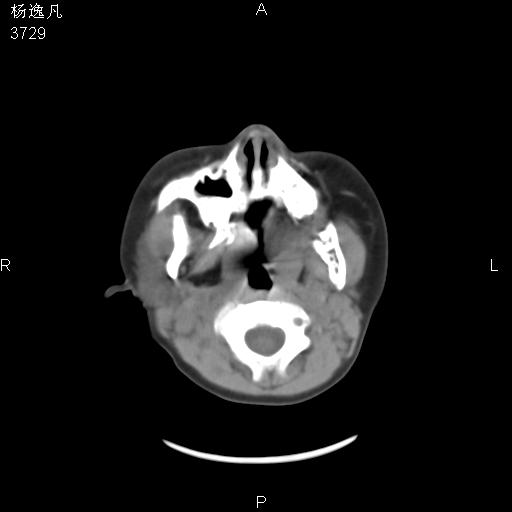

男性,5岁,面部受外伤,余无特殊

薄层

1、右面部及颞部软组织肿胀。

2、腺样体肥大。

头颅ct平扫未见明确外伤性征象,右侧面部及颞部软组织肿胀,后鼻腔软组织影增大,增厚,鼻咽顶部变窄,考虑鼻咽腺样体增值肥厚。